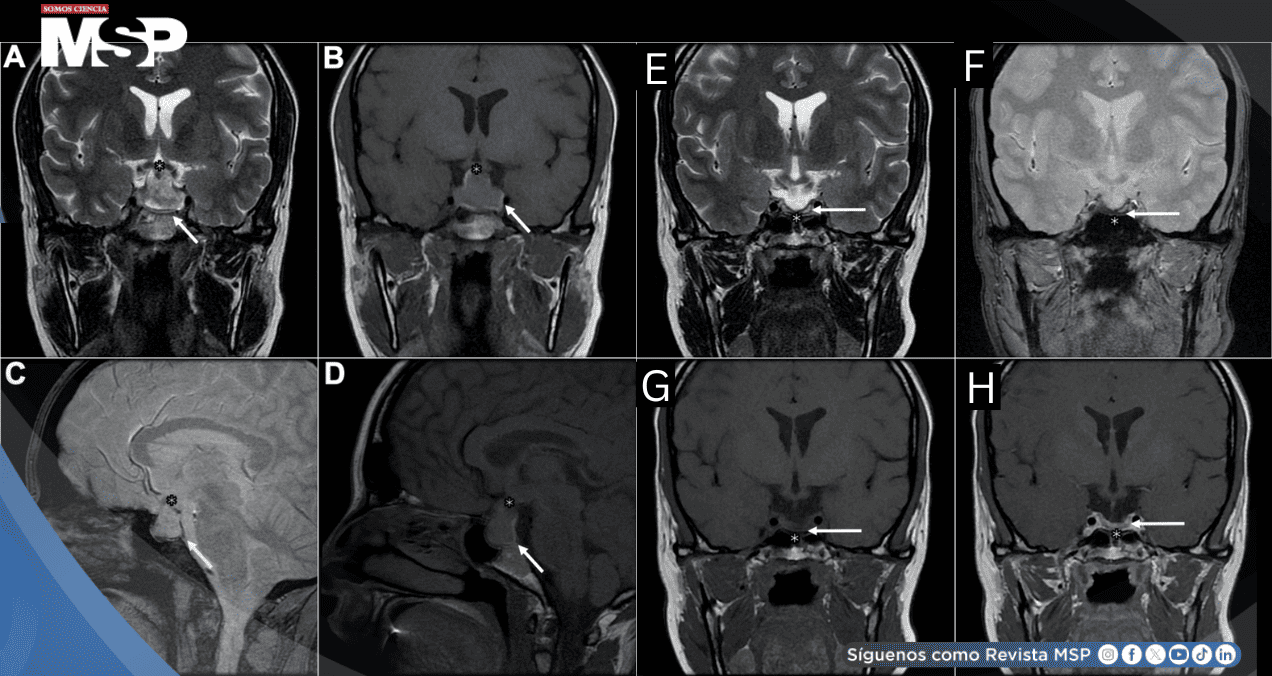

La tomografía computarizada no evidenció trombosis venosa cerebral, pero reveló agrandamiento del macroadenoma con componentes hiperatenuantes sugestivos de hemorragia, consistente con apoplejía hipofisaria.

La resonancia magnética confirmó el diagnóstico, demostrando crecimiento tumoral a 23×25×13.5 mm con extensión supraselar, desplazamiento del quiasma óptico y productos hemorrágicos agudos.

Permanece en terapia de reemplazo hormonal múltiple, incluyendo hormona de crecimiento iniciada al año con mejoría marcada en calidad de vida. La resonancia de seguimiento no mostró tumor residual.